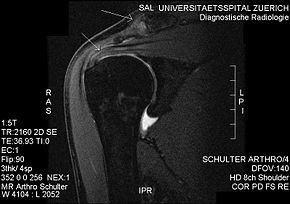

MRI showing subacromial impingement with partial rupture of the supraspinatus tendon, but no retraction or fatty degeneration of the supraspinatus muscle.

Plain x-rays of the shoulder can be used to detect some joint pathology and variations in the bones, including acromioclavicular arthritis, variations in the acromion, and calcification. However, x-rays do not allow visualization of soft tissue and thus hold a low diagnostic value.[2] Ultrasonography, arthrography and MRI can be used to detect rotator cuff muscle pathology. MRI is the best imaging test prior to arthroscopic surgery.[2] Due to lack of understanding of the pathoaetiology, and lack of diagnostic accuracy in the assessment process by many physicians,[18] several opinions are recommended before intervention.